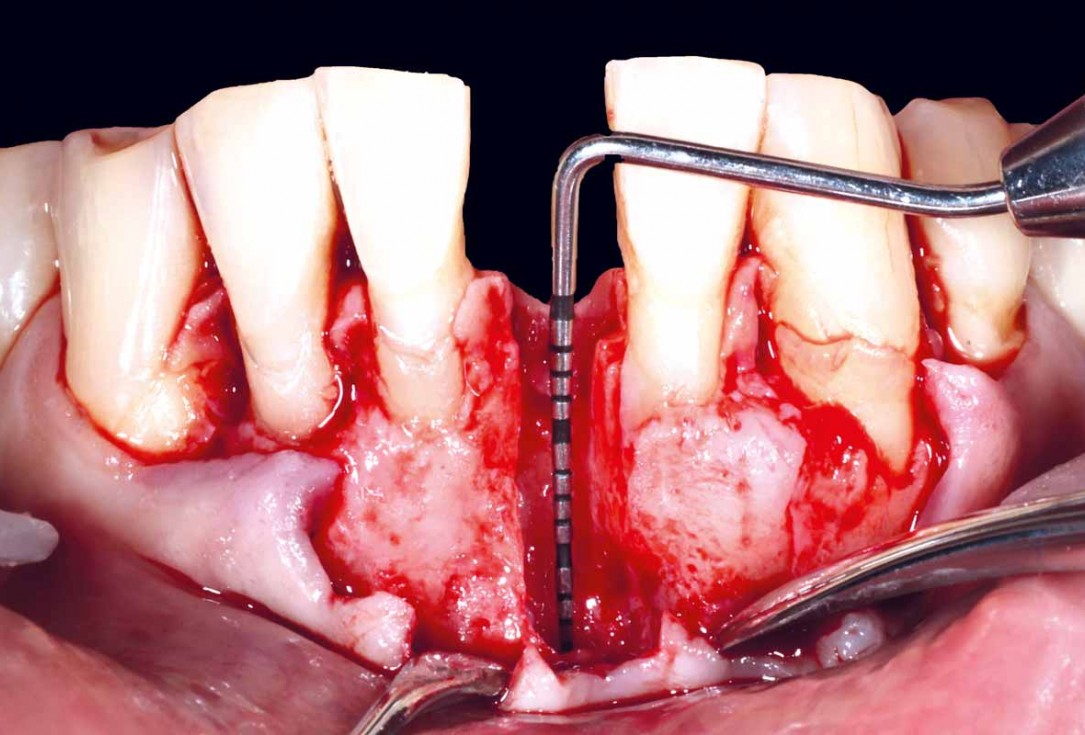

Pre-operative situation showing tooth 21 with deep periodontal pocket. Tooth presented with mobility grade III.